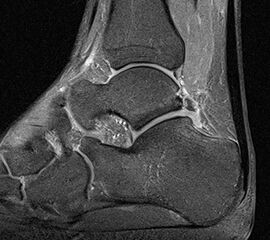

MRT

Die Kernspintomographie hat ihre Stärke in der Darstellung von Weichteilverletzungen. Insbesondere Verletzungen der Wachstumsfuge, des Periosts und der Bänder lassen sich gut visualisieren. Nachteilig ist die Untersuchungsdauer von 20-30 Minuten. Bleibt das Kind während dieser Zeit nicht ruhig liegen, kommt es zu Bewegungsartefakten, welche die Beurteilbarkeit der Bilder beeinträchtigen.

Os subfibulare

Multiple laminäre Ausrisse des fibularen Bandapparats aus der Fibulaspitze können zur Entwicklung eines Os subfibulare führen. Das Os subfibulare findet sich unterhalb der Fibulaspitze ventral der Peronealsehnen. Ohne Schmerzsymptomatik bzw. Aktivierung im MRT hat Das Os subfibulare keinen Krankheitswert. Ein mobiles Os subfibulare führt zu einer lokalen mechanischen Reizung teilweise in Verbindung mit einer Instabilität des Sprunggelenks. Im MRT zeigt sich eine Aktivierung des instabilen Areals. Bei anhaltenden Schmerzen besteht die Behandlung in einer operativen Entfernung des Knochens mit Refixation des Kapselbandapparats.

Os trigonum

Das Os trigonum lässt sich als isolierter Knochen dorsal des Talus seitlichen Röntgenbild darstellen. Normalerweise hat das Os trigonum keine klinische Relevanz. Bei entsprechenden Beschwerden und einer Aktivierung im MRT kann der Knochen arthroskopisch entfernt werden. Gehäuft beobachten wir eine mechanische Problematik durch das Os trigonum bei jugendlichen Fußballspielern und Tänzerinnen.